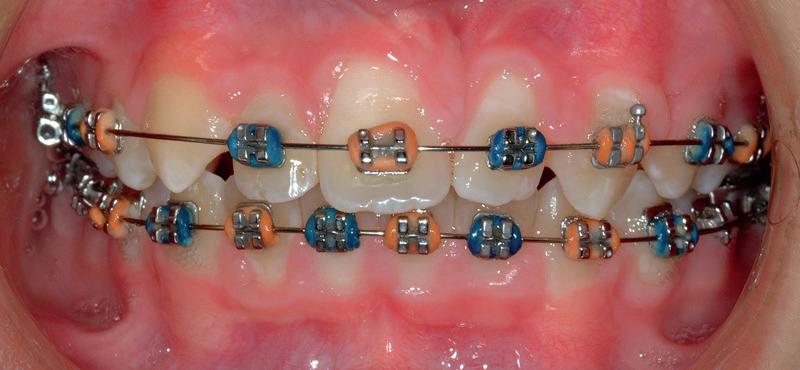

Am selectat pentru acest număr al revistei, dedicat ca în fiecare septembrie implantologiei, o serie de prezentări de caz axată pe tehnici dovedite în terapia implantară:

RECONFIGURAREA suportului osos implantar. În cazul prezentat, după ani de terapie ortodontică incorect executată, dezvoltarea dentară a pacientului a complicat obținerea unui zâmbet estetic. S-a reanalizat și s-a optat pentru abordare interdisciplinară care cuprinde chirurgia parodontală, un al doilea tratament

ortodontic și protetica pentru a oferi îngrijirea comprehensivă.